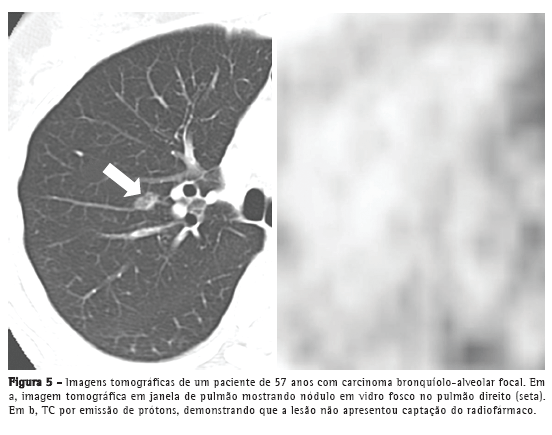

A positron emission tomography (PET, tomografia por emissão de prótons) é tida como ferramenta fundamental no estadiamento, tratamento e seguimento de neoplasias pulmonares (Figura 4). Entretanto, deve-se enfatizar que os CBA puros podem não demonstrar hiperconcentração de 18F fluordesoxiglicose (FDG),(6) dado que esses tumores são usualmente indolentes, de crescimento lento e bem diferenciados. Logo, a ausência de captação do FDG não exclui a possibilidade de neoplasia, tais como CBA, pequenas lesões ou neoplasias indolentes. Martins et al.(17) estudaram a acurácia diagnóstica da PET na avaliação de nódulos pulmonares solitários e, dentre os 32 pacientes estudados, obtiveram somente um resultado falso-negativo, cujo diagnóstico final foi de CBA. Sendo assim, a análise do aspecto tomográfico é mandatória para o diagnóstico (Figura 5).